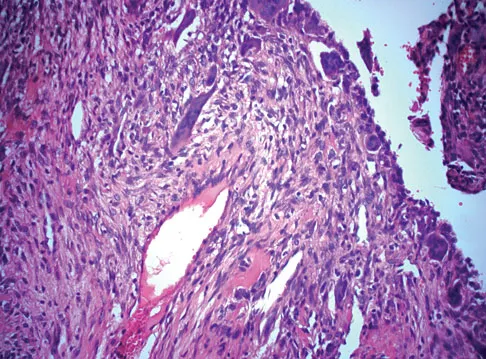

<span class="exp-title">Detailed Explanation</span><div markdown="1">In the initial assessment of acute low back pain in adults, no diagnostic testing is indicated during the first 4 weeks in the absence of "red flags" for a serious underlying condition. The purpose of the initial assessment of acute low back pain in adults is to rule out serious underlying conditions presenting as low back pain. The Agency for Healthcare Policy and Research, in its 1994 clinical practice guideline, identified four serious conditions that may present with low back pain, including fracture, tumor, infection, and cauda equina syndrome. This patient has five "red flags" for a spinal tumor as a possible etiology of his low back pain, including age of older than 50 years, constitutional symptoms (recent weight loss), pain worse when supine, severe nighttime pain, and a history of cancer. Of these, his history of cancer is most significant, as greater than 90% of spinal tumors are metastatic. In order of frequency, breast, prostate, lung, and kidney make up approximately 80% of all secondary spread to the spine. In the presence of "red flags" for tumor or infection, it is recommended that the clinician obtain a CBC count, ESR, and a urinalysis. If these are within normal limits and suspicions still remain, consider consultation or seek further evidence with a bone scan, radiographs, or additional laboratory studies. Negative radiographs alone are insufficient to rule out disease. If radiographs are positive, the anatomy can be better defined with MRI. Agency for Health Care Policy and Research, Bigos SJ (ed): Acute Low Back Problems in Adults. Rockville, MD, US Department of Health and Human Services, AHCPR Publication 95-0642, Clinical Practice Guideline #14, 1994.